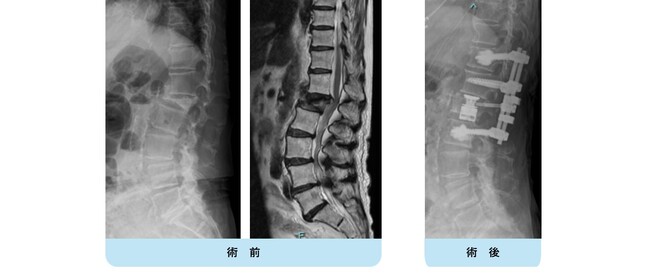

【術前】

第2, 第3, 第4腰椎に前方への変性すべりを認めます。痛みのため背中を反って立てないことが分かります。MRIではいずれの椎間でも強い脊柱管狭窄が発生し、神経が圧迫されているのが分かります。

【術後】

スクリューとロッド、人工骨を使用した手術により腰椎の階段状変性すべりが整復され、痛みが改善したため腰を反って立つことが出来ています。第2腰椎の前方すべりは軽微であったため、金属は使わず除圧術のみに留めています。